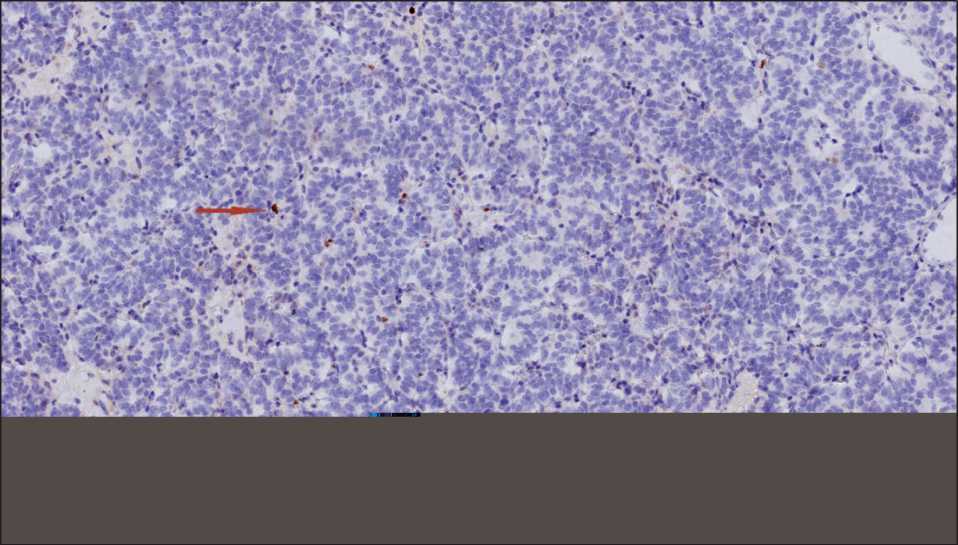

Рис. 4. ИГХ-исследование. Индекс Ki67 равномерный, невысокий – до 2 % (стрелками обозначены единичные позитивные клетки), ×10. Примечание: рисунок выполнен авторами

Fig. 4. Microphoto. IHC study. Ki67 index is uniform, low, up to 2 %; ×10. The arrows indicate single positive cells.

Note: created by the authors

ферации по уровню экспрессии маркера Ki67 был равномерным и невысоким до 2 % (рис. 4). На основании морфологической картины подтвержден типичный карциноид нижней доли правого легкого T2aN0M0 IB стадии.